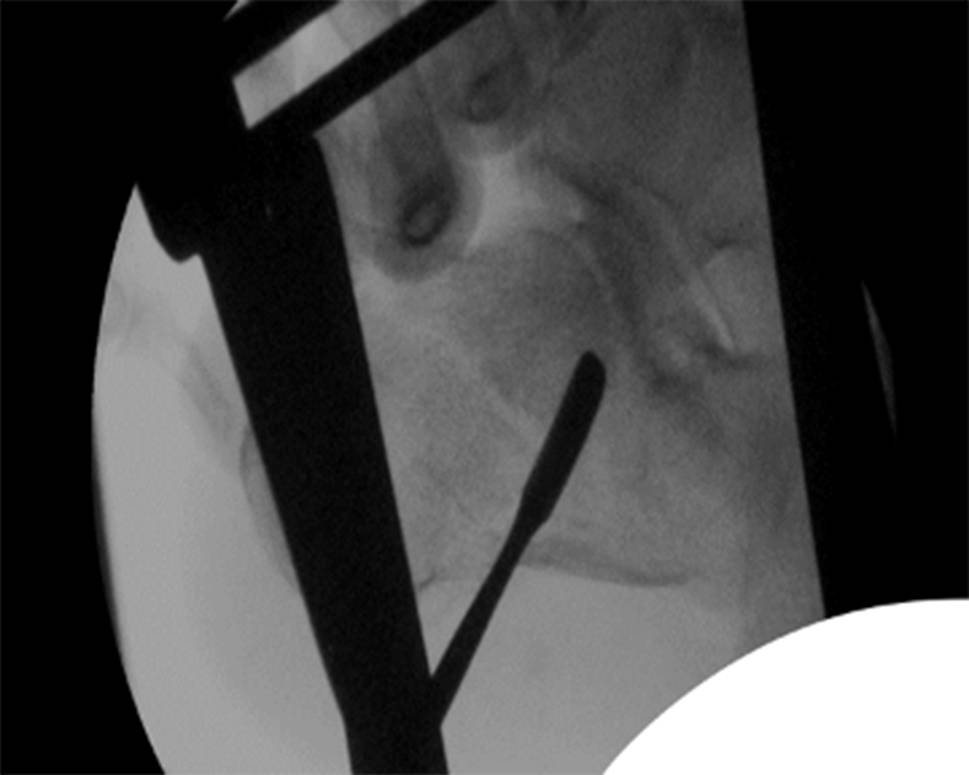

Early surgery was performed if the tissue conditions were adequate. The patient was placed in a lateral position with the fractured side up, close to the edge of the operating table. Standard lateral and Broden view radiographs were obtained. A 3 mm K-wire was positioned perpendicular to the subtalar joint on the lateral view and two 3 mm K-wires were separately placed perpendicularly to the calcaneal axis in the talus neck and into the calcaneal tuberosity. Subsequently, the Fröhlich traction device (ITS Implants, Autal, Laßnitzhöhe, Austria) was assembled on both sides of the calcaneus and traction was gradually initiated. The subtalar joint traction was monitored by lateral view. Through a lateral incision, a raspatory or drill wire is used to lift and reduce the dislocated and impressed parts of the posterior joint facet (Fig. 1).

Fig. 1

Broden View of the posterior joint facet